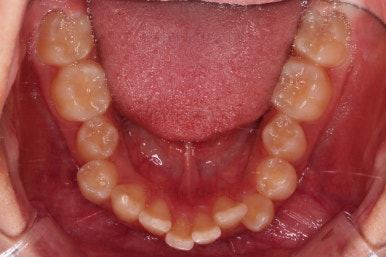

동래교정치과 초진 시의 입 안 모습이에요.

치열이 삐뚤고 덧니가 보이네요.

이번 환자분도 스스로는 보기 싫은 이유가 첫 번째였지만 사진에서도 보시다시피 양치가 잘 안되어 치석도 많고 잇몸도 부어있는 상태였어요.

그리고 앞니들이 마모가 많이 되어 있어서 각각의 치아들이 원래 형태에서 많이 변형된 것을 볼 수 있네요.

장치를 부착했어요.

윗니는 상대적으로 많이 보이기 때문에 세라믹, 아랫니는 많이 보이지 않기 때문에 메탈로 부착했어요.

치여링 가지런해졌고, 교합과 중앙선 등 입안의 모습이 매우 좋아졌어요.

불규칙하게 마모되어 있던 치아의 개별 형태도 약간씩 다듬어 드렸고요.